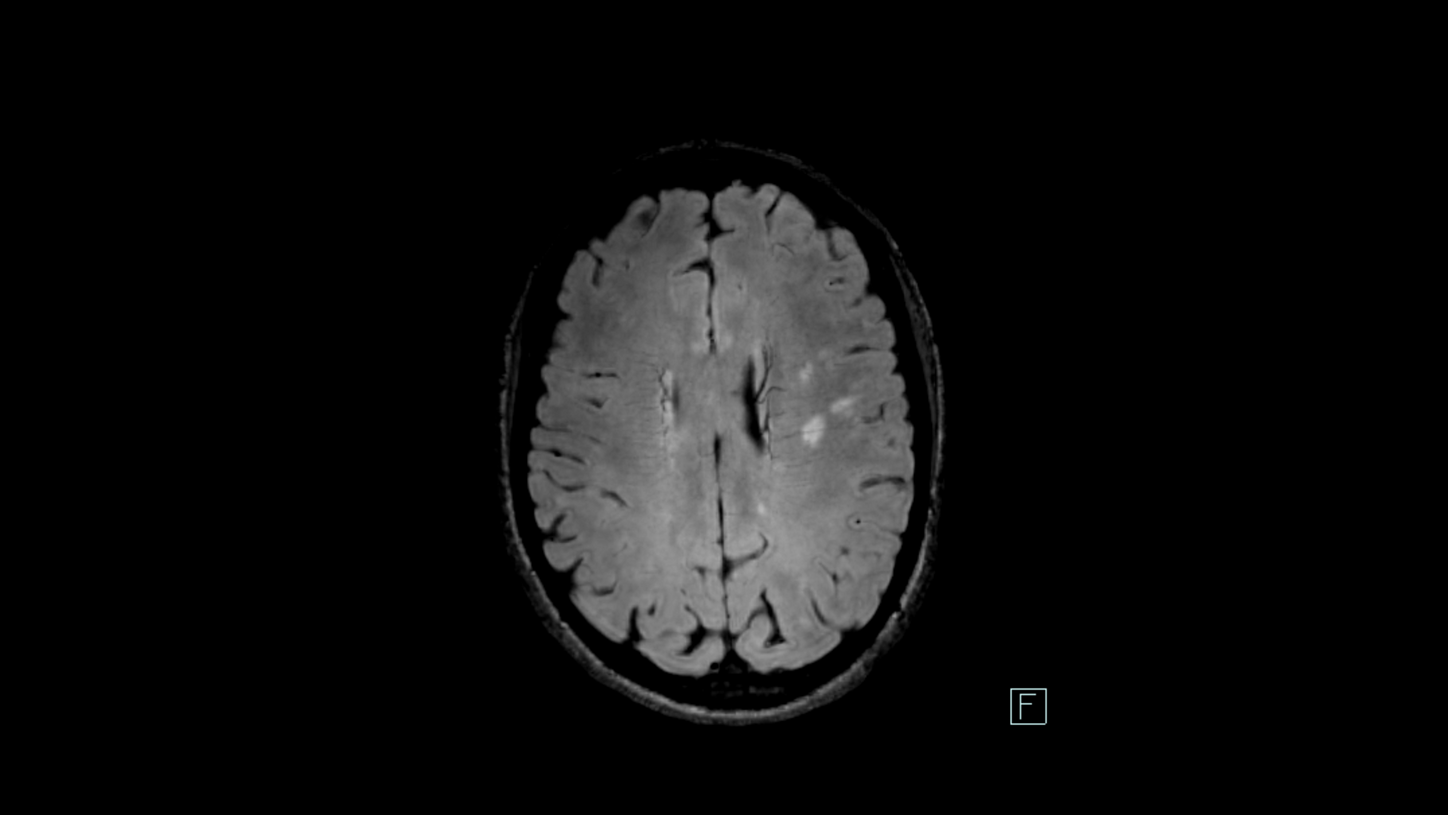

Dissemination in time (DIT)

New lesions at two different points in time

DIT refers to the development of new lesions within the CNS over time, meaning that during different time points of MRI follow-up new lesions can be found which have not been seen before. DIT can be demonstrated via new WMH on T2-weighted imaging as shown above, or new contrast-enhancing lesions in T1-weighted MPRAGE.